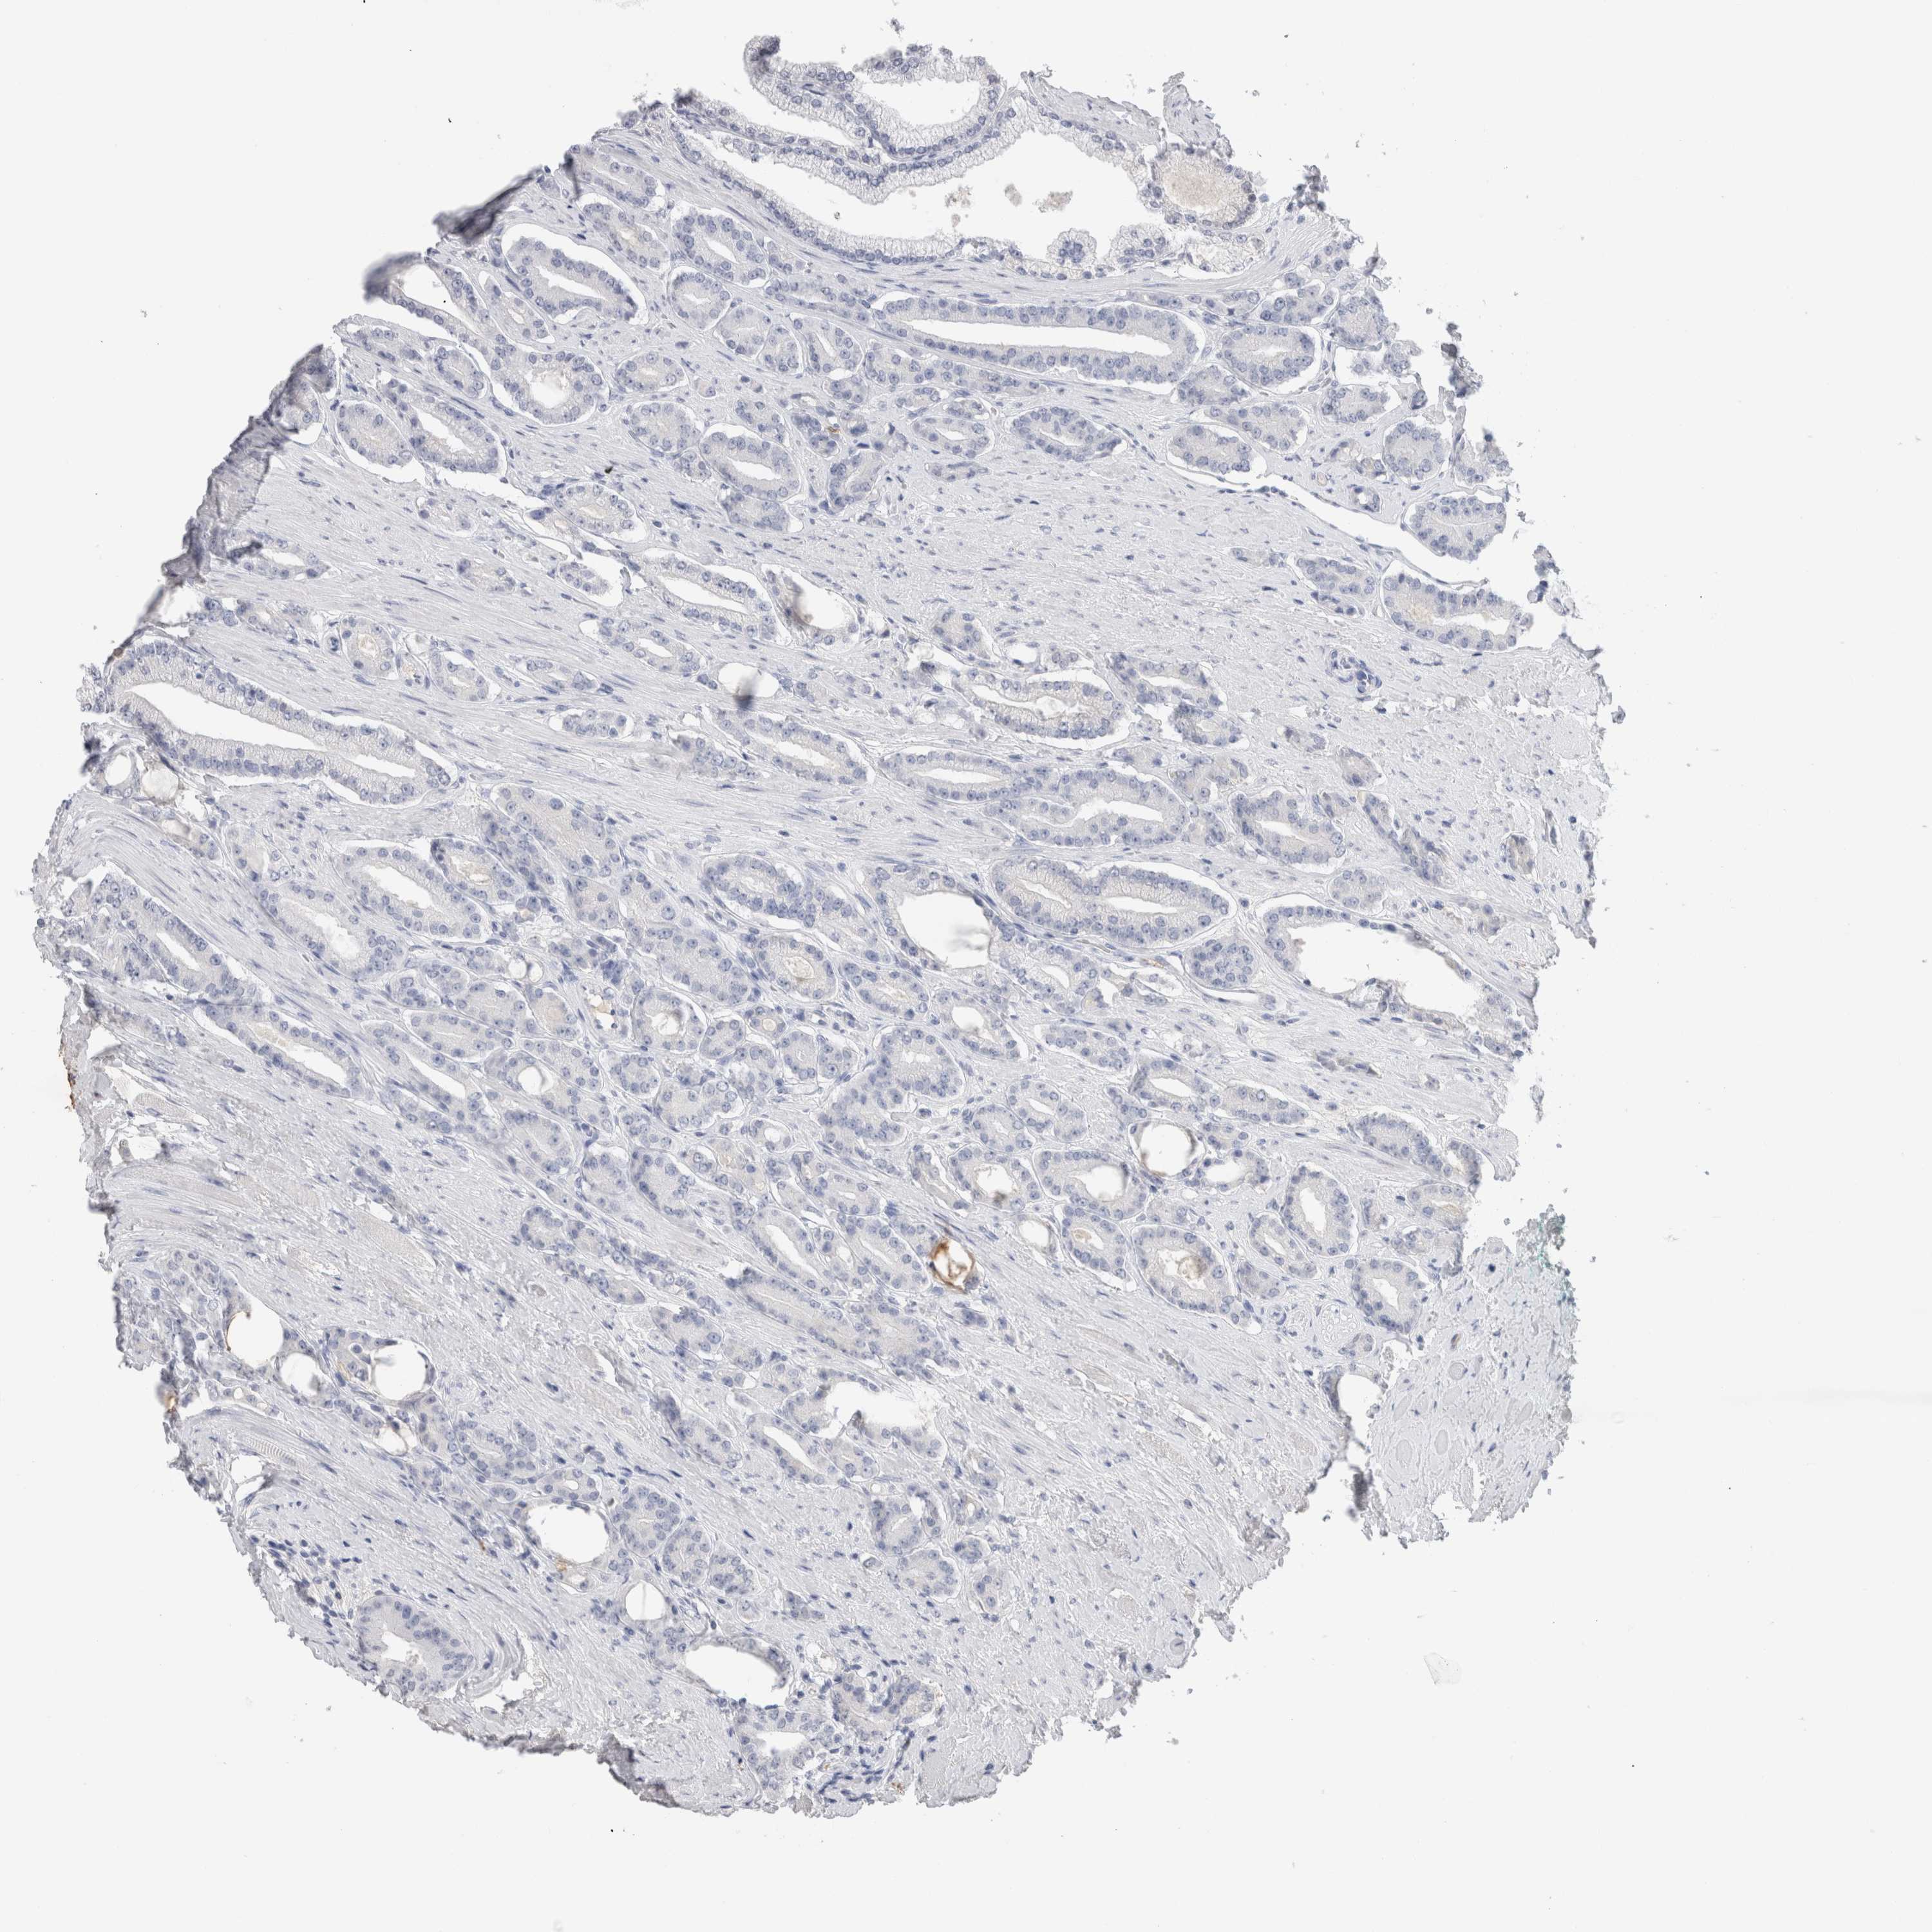

PROSTATE CANCER - Protein expressioni

A mouse-over function shows sample information and annotation data. Click on an image to view it in a full screen mode. Samples can be filtered based on level of antibody staining by selecting one or several of the following categories: high, medium, low and not detected. The assay and annotation is described here.

Antibody stainingi

Antibody staining in the annotated cell types in the current human tissue is reported as not detected, low, medium, or high, based on conventional immunohistochemistry profiling in selected tissues. This score is based on the combination of the staining intensity and fraction of stained cells.

Each image is clickable and will lead to virtual microscopy that enables deeper exploration of all samples and also displays staining intensity scores, fraction scores and subcellular localization as well as patient and tissue information for each sample.

Antibody HPA051467

Antibody CAB025133

Staining

High

Medium

Low

Not detected

Intensity

Strong

Moderate

Weak

Negative

Quantity

>75%

75%-25%

<25%

None

Location

Nuclear

Cytoplasmic/membranous

Cytoplasmic/membranous,nuclear

Adenocarcinoma, NOS

Adenocarcinoma, High grade

Adenocarcinoma, Low grade